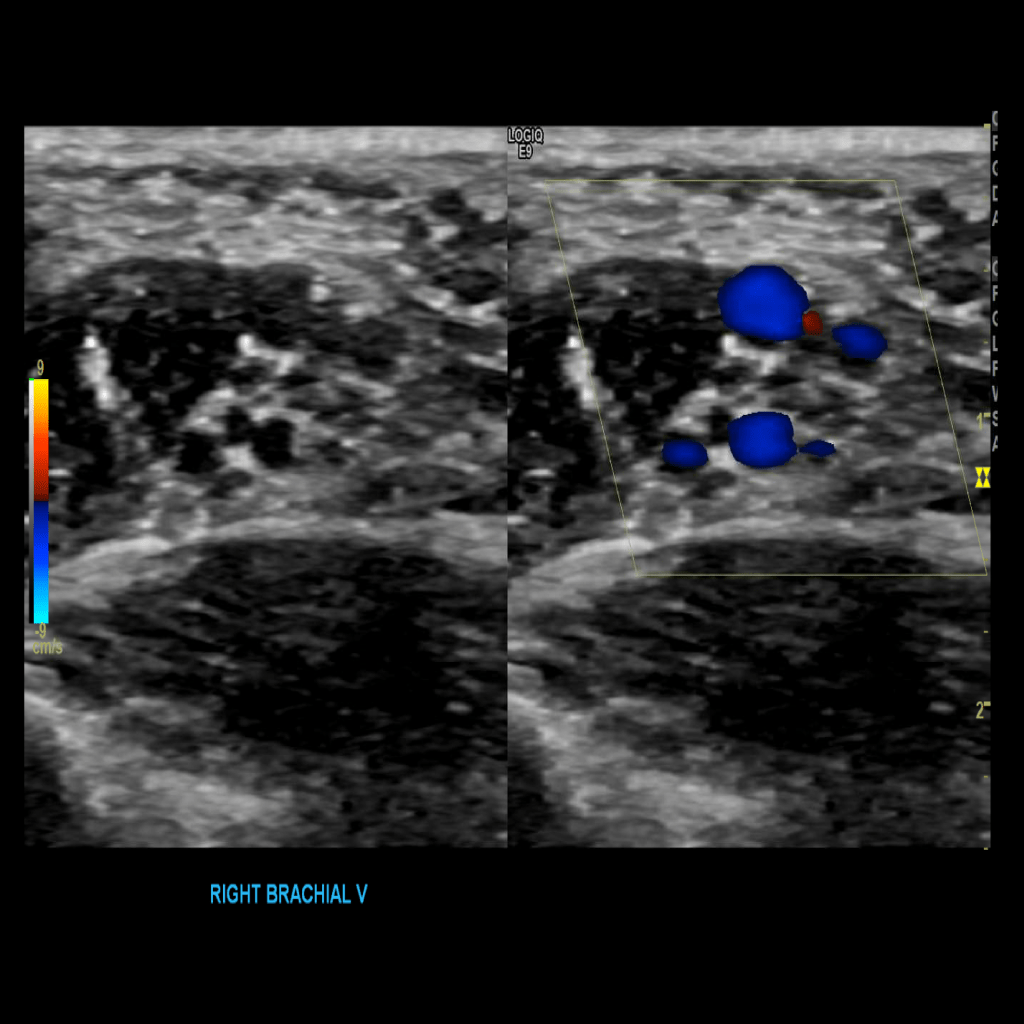

Scan the brachial veins in grey scale, compression, color doppler and spectral doppler

Brachial vein thrombosis